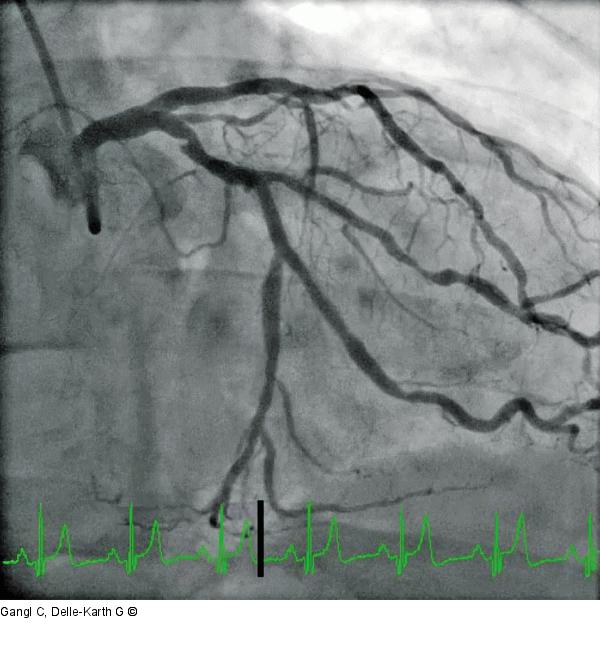

Abbildung 1: Proximale A. cricumlexa Kontrasmittelaussparung in der proximalen CX |

Abbildung 1: Proximale A. cricumlexa